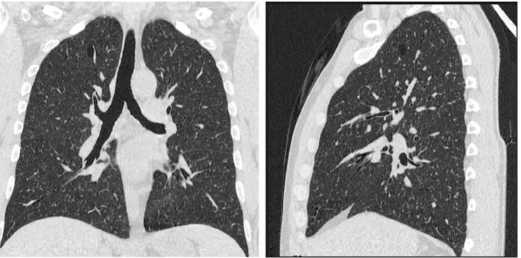

снижение объема мочевого пузыря до 50 мл, утолще ние его стенок до 10мм.По данным компьютерной то мографии (КТ) органов дыхания картина диссемини рованного туберкулеза легких (рис. 1). На КТ органов брюшной полости с контрастным усилением двухсто ронняя уретероэктазия, более выраженная слева, мик роцистис, утолщение стенок мочевого пузыря (рис. 2) КТ головного мозга выявила мелкие гиперваскулярные очаги в левой гемисфере (рис. 3).

Рис. 1. Больной Ж. КТ органов грудной клетки: диссеминированный процесс в легких, киста правого легкого

Fig. 1. Patient J. Сhest CT: disseminated process in the lungs and a cyst in S1 of the right lung